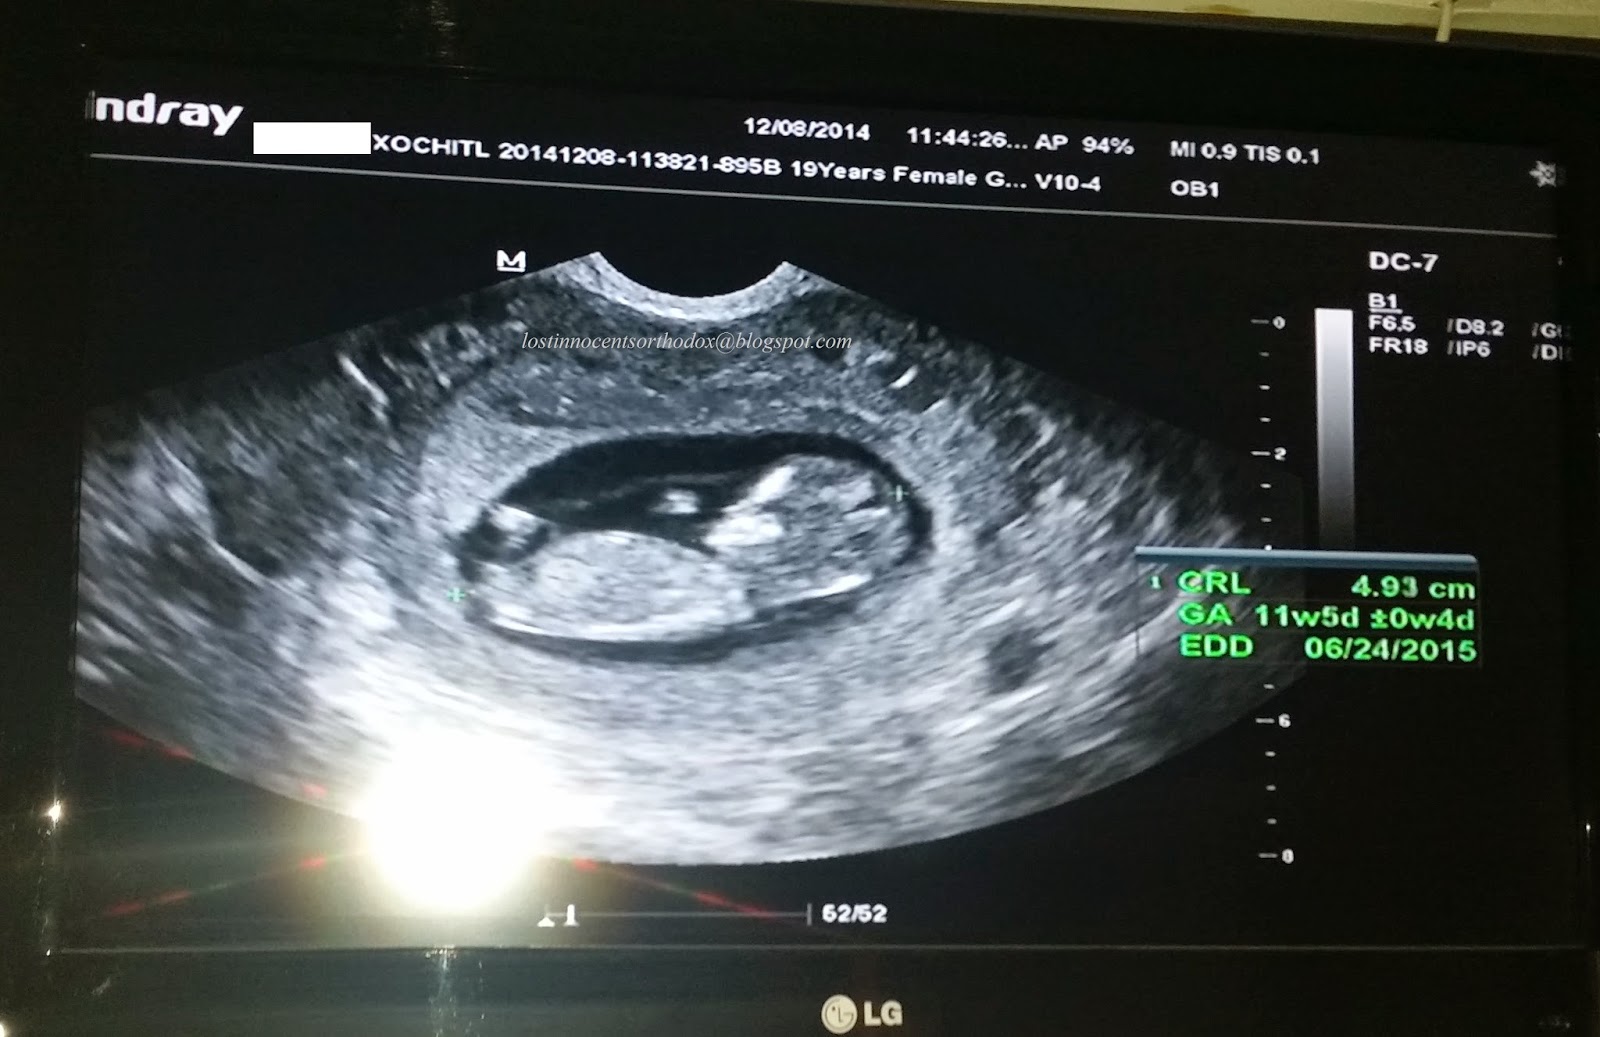

At the beginning of January 2015, we learned I was pregnant. My husband and I had been trying for 12 months since the loss of our first, due to an ectopic pregnancy I experienced just weeks after we got married. I had surgery to remove one of my tubes, and lost our first precious baby on October 1, 2013. I named him shortly after discovering your website “Protection”, as he was delivered on the Feast of the Holy Protection of the Theotokos. I was approximately 6wks 4 days at the time. When I got pregnant with our second (I named her “Forgiveness”), I was elated! I remember taking the pregnancy test that morning in our bathroom home alone (for probably the 30th time in the last 12 months), thinking it would be another negative result. When a saw the second line come up and realized what wonderful miracle had happened, I remember I just looked up at the ceiling and said “Thank you Lord” through tears of joy. As a precaution, I had an ultrasound to confirm that our baby was in my uterus (that was done at 5 wks 2 days), as I was at a higher risk of experiencing another ectopic. I had a gut feeling that this was a little girl. I was so sure, but did not know why. With the first pregnancy I did not have any such gut feeling, so I decided that my first must have been a boy. Only God really knows I guess.